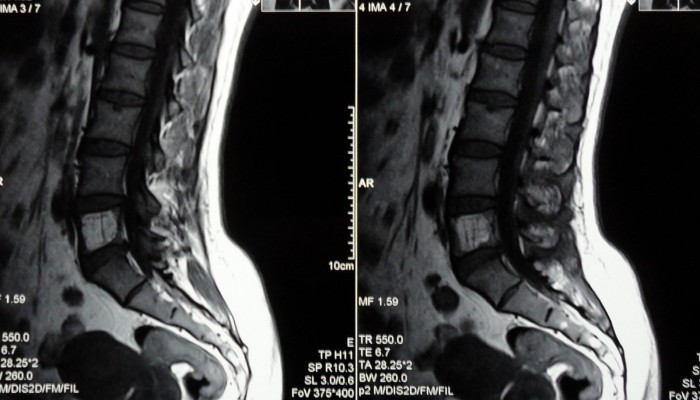

Подтвердить стеноз позвоночного канала можно только после дополнительного обследования. Оно должно включать методы визуализации, которые позволят выяснить происхождение сужения, оценить его размер и распространенность, проанализировать состояние окружающих тканей. Подобными свойствами обладают следующие процедуры:

- Магнитно-резонансная томография – на продольных срезах четко видно очаг поражения и состояние мягких тканей.

- Компьютерная томография – на послойных изображениях можно выявить структурные нарушения и определить размеры спинномозгового канала.

- Рентгенография – на снимке можно увидеть изменение высоты межпозвонкового пространства, смещения и деформации костных структур.